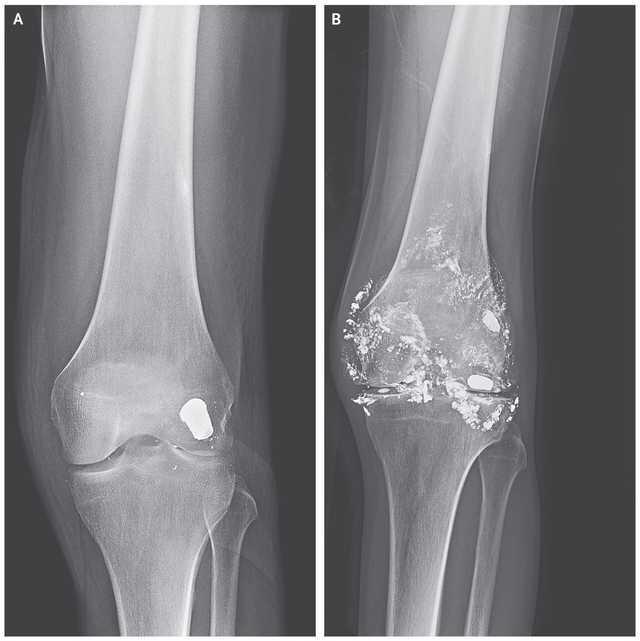

Kość i ołów z pocisku (B)